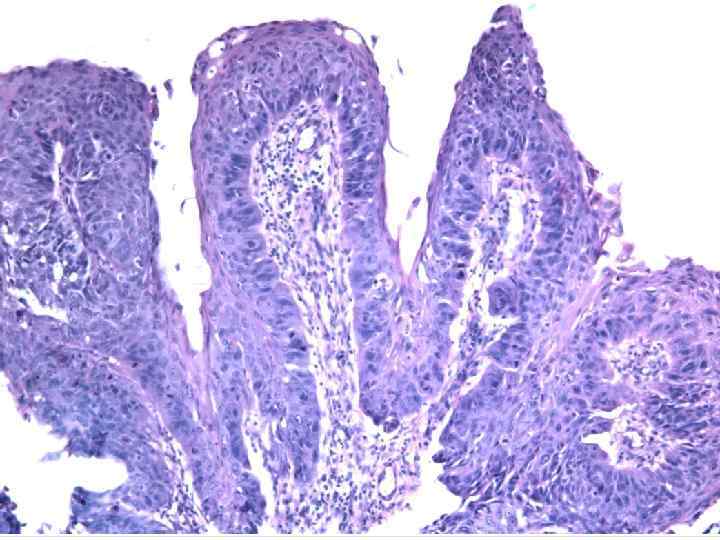

Syringoadenoma